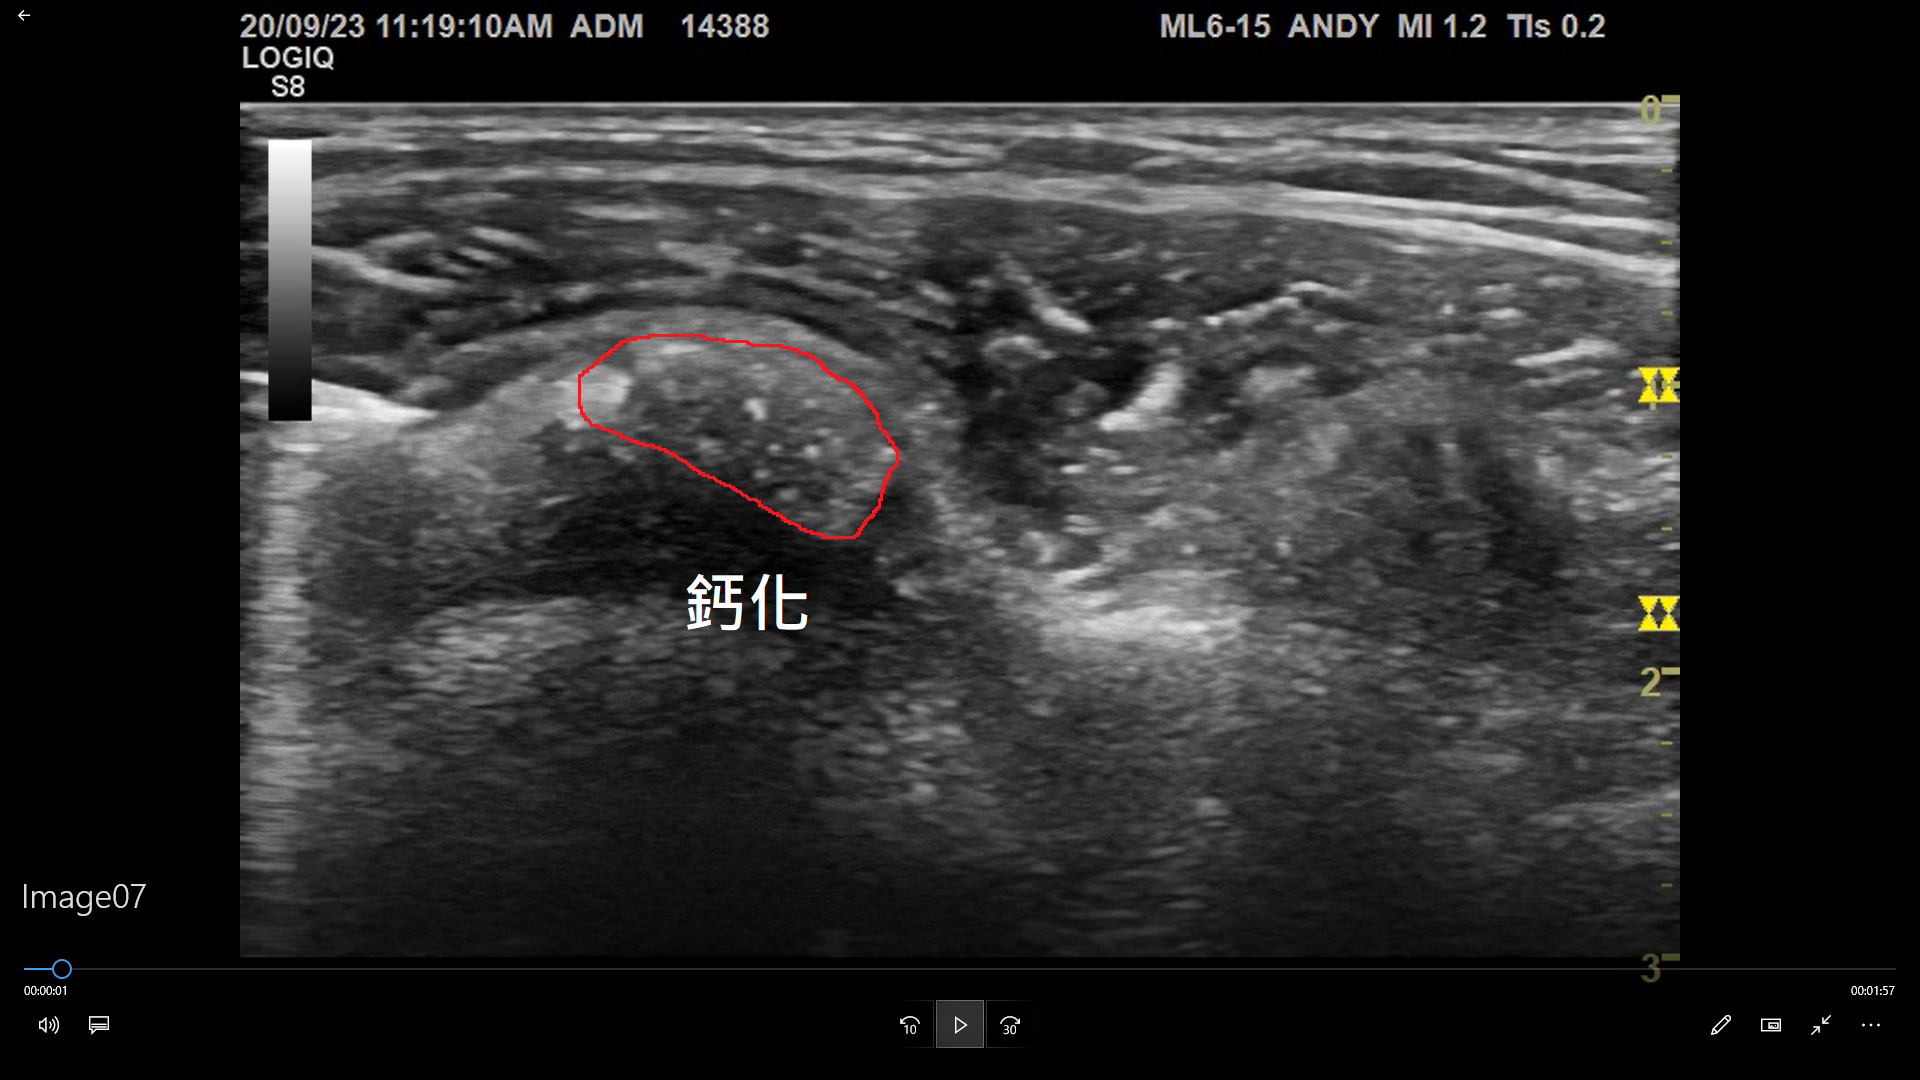

急性的肩膀疼痛需要和旋轉肌肌腱撕裂做鑑別診斷,這時候超音波就是一個最好的診斷工具。在超音波掃描下,肌腱可以區分究竟是撕裂傷、鈣化、甚至兩者都有。X光也可以看到鈣化的區域,但無法區別有沒有肌腱撕裂、也沒辦法辨別鈣化在什麼狀態,因此和超音波相比比較不準確。

超音波掃描,鈣化一覽無遺